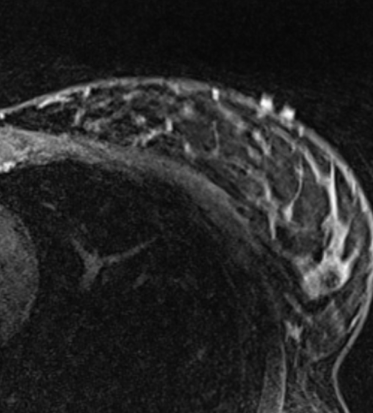

An MRI with the woman lying on her back is done with the breast positioned as it will be during surgery, so the exact detail of the size, shape, depth, and edges of the tumor can be seen.

This image is used to analyze the tumor and build a three-dimensional model of the tumor and breast. This offers the surgeon the view of the breast and tumor in the same position as it will be during surgery.